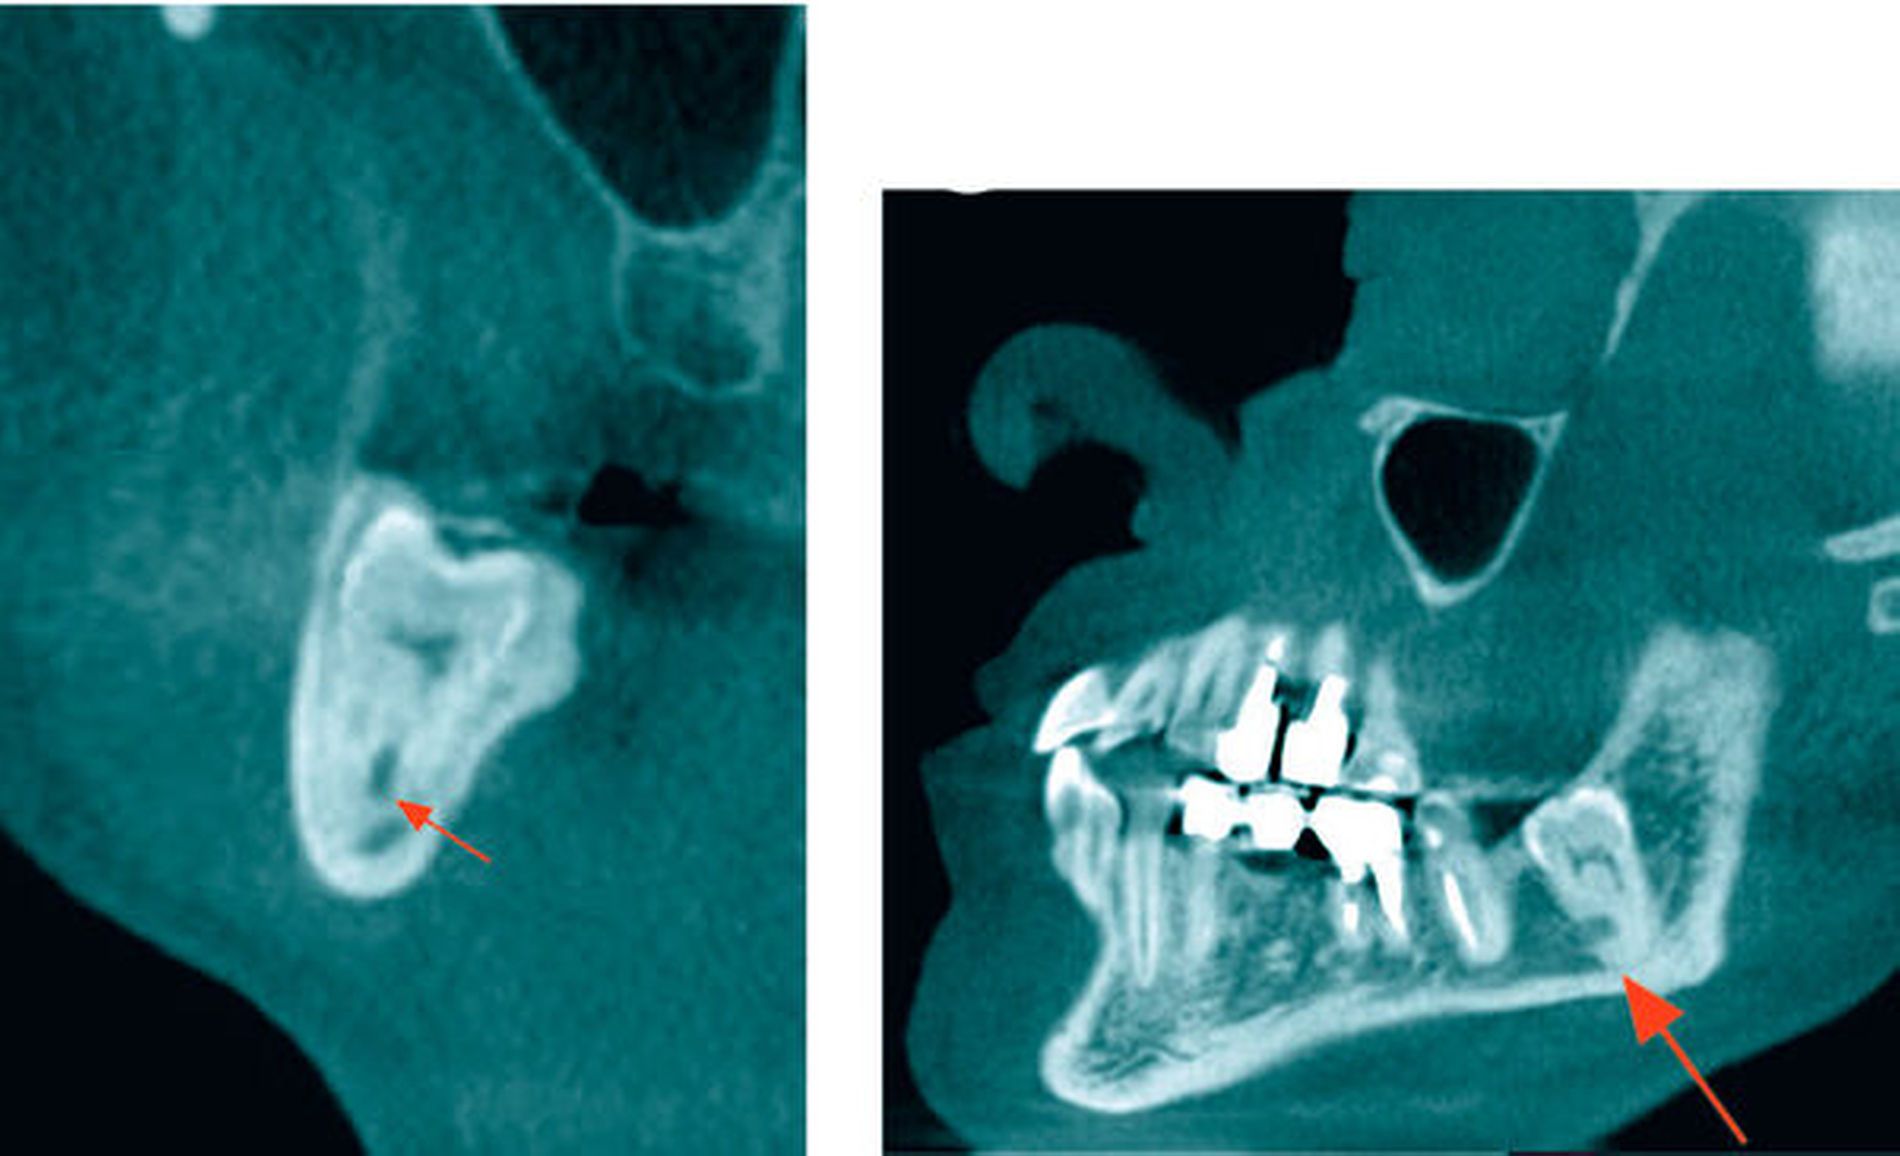

In der koronaren und der sagittalen Schicht des DVT zeigte sich deutlich die Lage beider Apices in der kaudalen Kompakta des Corpus mandibulae. Zudem wurde ein intraradikulärer Verlauf des Canalis mandibularis rechts durch die Wurzeln des 48 (Abbildung 2) erkannt. Am ebenfalls tief retinierten Zahn 38 konnte relativ zur Wurzel des Zahnes 38 ein lingualer Verlauf des Canalis mandibularis verifiziert werden (Abbildung 3).